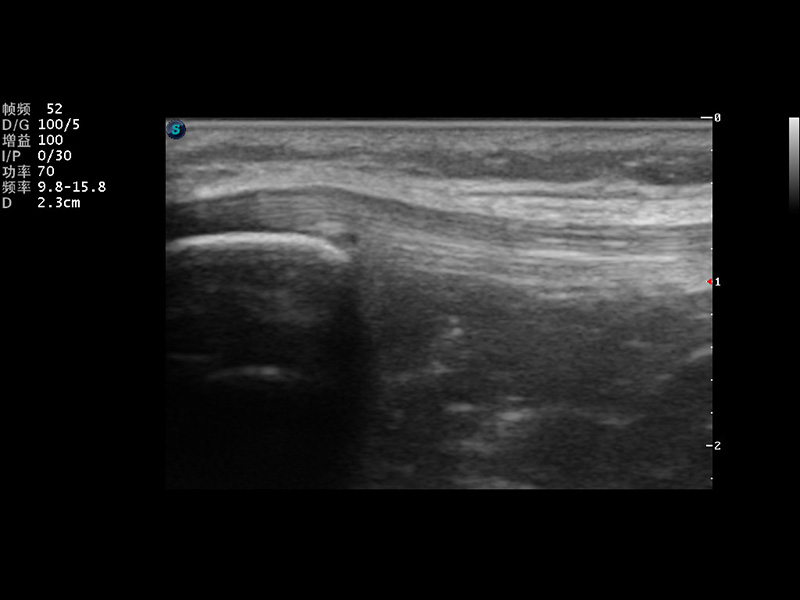

正常肺脏